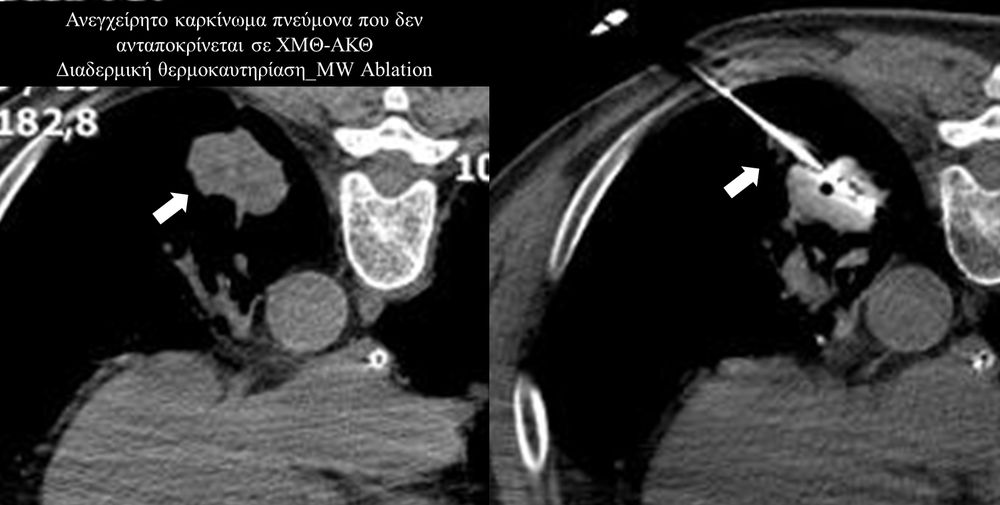

Πρόκειται για την πιο σύγχρονη τοπική θεραπεία όγκων του ήπατος, του νεφρού, του πνεύμονα, των οστών και των όγκων μαλακών μορίων. Παθοφυσιολογικά βασίζεται στην τοπική καταστροφή των καρκινικών κυττάρων με τη δημιουργία ιδιαίτερα υψηλών θερμοκρασιών εντός του όγκου. Αυτό επιτυγχάνεται με τοποθέτηση ειδικών ηλεκτροδίων εντός του όγκου υπό ακτινολογική καθοδήγηση (αξονικός τομογράφος ή υπέρηχος). Τα ηλεκτρόδια αυτά παράγουν υψηλή θερμοκρασία είτε με τη βοήθεια ραδιοσυχνοτήτων (RFablation), είτε με τη βοήθεια μικροκυμάτων (MWablation) και προκαλούν πηκτική νέκρωση των καρκινικών κυττάρων χωρίς να επηρεάζουν τα φυσιολογικά κύτταρα.Το αποτέλεσμα είναι μόνιμο.